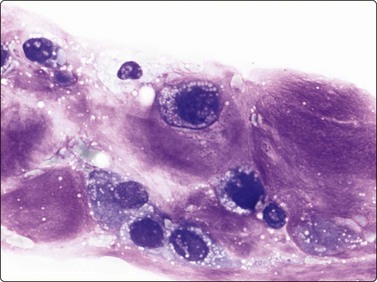

The cytological appearance of conventional ES is distinctive. Smears are generally highly cellular and are composed of both single cells and groups of loosely cohesive cells. The cells are fragile and naked nuclei as well as a faint gray–blue (MGG) background of detached cytoplasm are commonly seen. There is a characteristic mixture of two types of cells. One has abundant pale cytoplasm with vacuoles or large clear spaces, rounded or ovoid nuclei with finely granular chromatin and 1–3 small nucleoli (‘large light cells’). The other has scanty cytoplasm and irregular nuclei with dense chromatin (’small dark cells’). The two types of cells are most clearly distinguished within groups or clusters of cells, the small dark cells are interspersed, often as small molded groups, between large light cells (Fig. 16.31A). Rosette-like structures without a fibrillar center are occasionally present (Fig. 16.31B,C). The cytoplasmic vacuoles or clear spaces correspond to large deposits of glycogen (Fig. 16.31A).

image image image

Fig. 16.31 Ewing’s sarcoma

(A) A mixture of cells with larger pale-staining nuclei and cells with smaller and darker nuclei; note the cytoplasmic vacuoles and clear spaces in the pale cells (MGG, HP); (B,C) Rosette-like structure; nuclear chromatin and nucleoli more clearly seen in H&E than in MGG (A, H&E, HP; B, MGG, HP).